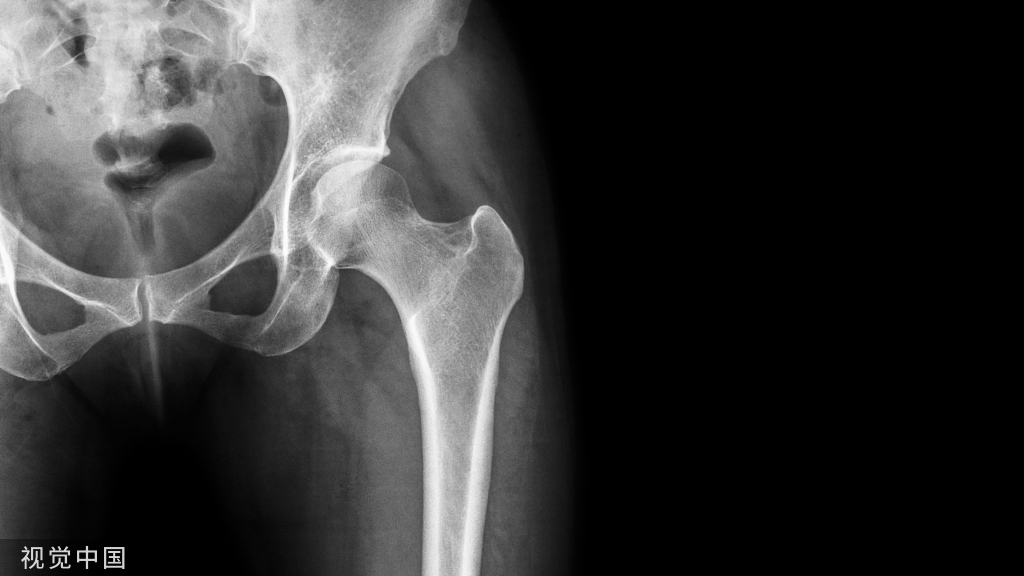

3.颊侧翼缘区(buccal flange area)

又称颊棚区,位于下颌后弓区,在下颌颊系带至咬肌下段前缘之间。

牙槽嵴吸收严重时,此区较为平坦,骨小梁排列与牙合力方向几乎呈直角。

基托可较大范围伸展,稳定义齿